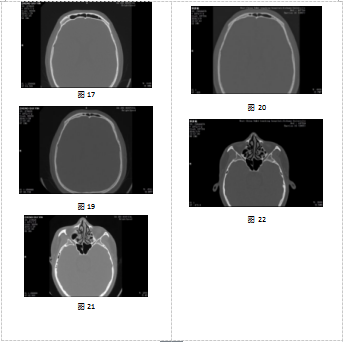

1月29日图像与3月9日图像比较,存在以下共同特征:①咬合时上下牙列形态及相对形态一致,其中右侧中切牙向内侧错位(见图3、4);②右下第二磨牙病变一致(见图5、6);③双侧上颌窦形态及慢性炎症改变一致(见图7、8);④右侧鼻骨骨皮质不连部位一致(见图9、10);⑤筛窦上部间隔分布位置及形态一致(见图11、12、13);⑥额窦左右共五个完整间隔,间隔附着位置及分隔的窦腔形态一致(见图14、15、16);⑦额窦右侧额骨气化形态一致(见图17、18);⑧额窦层面右侧顶骨形态一致(见图19、20);⑨蝶窦中间隔完整,右侧腔小于左侧腔,左右腔内另有不完整间隔均位于左侧壁,间隔位置及形态一致(见图21、22)。